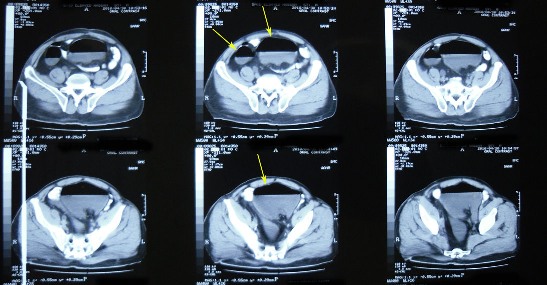

treatment. By difficulty we persuaded him to do ascending urography

" see photos".